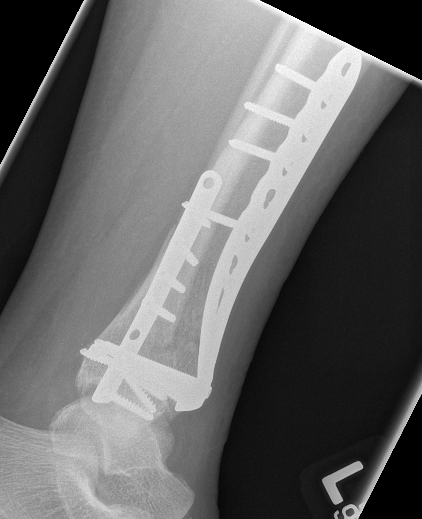

B. Distal Tibial ORIF with plate

Indications

- too distal to nail

- very comminuted / unstable

- intra-articular extension

Technique

1. Consider fixing the fibula

- will aid reduction / avoid malunion

- help control very unstable fractures

2. Anatomically contoured plates

- options of medial plate v anterolateral plate

- medial plate for varus deformity

- anterolateral plate for valgus deformity